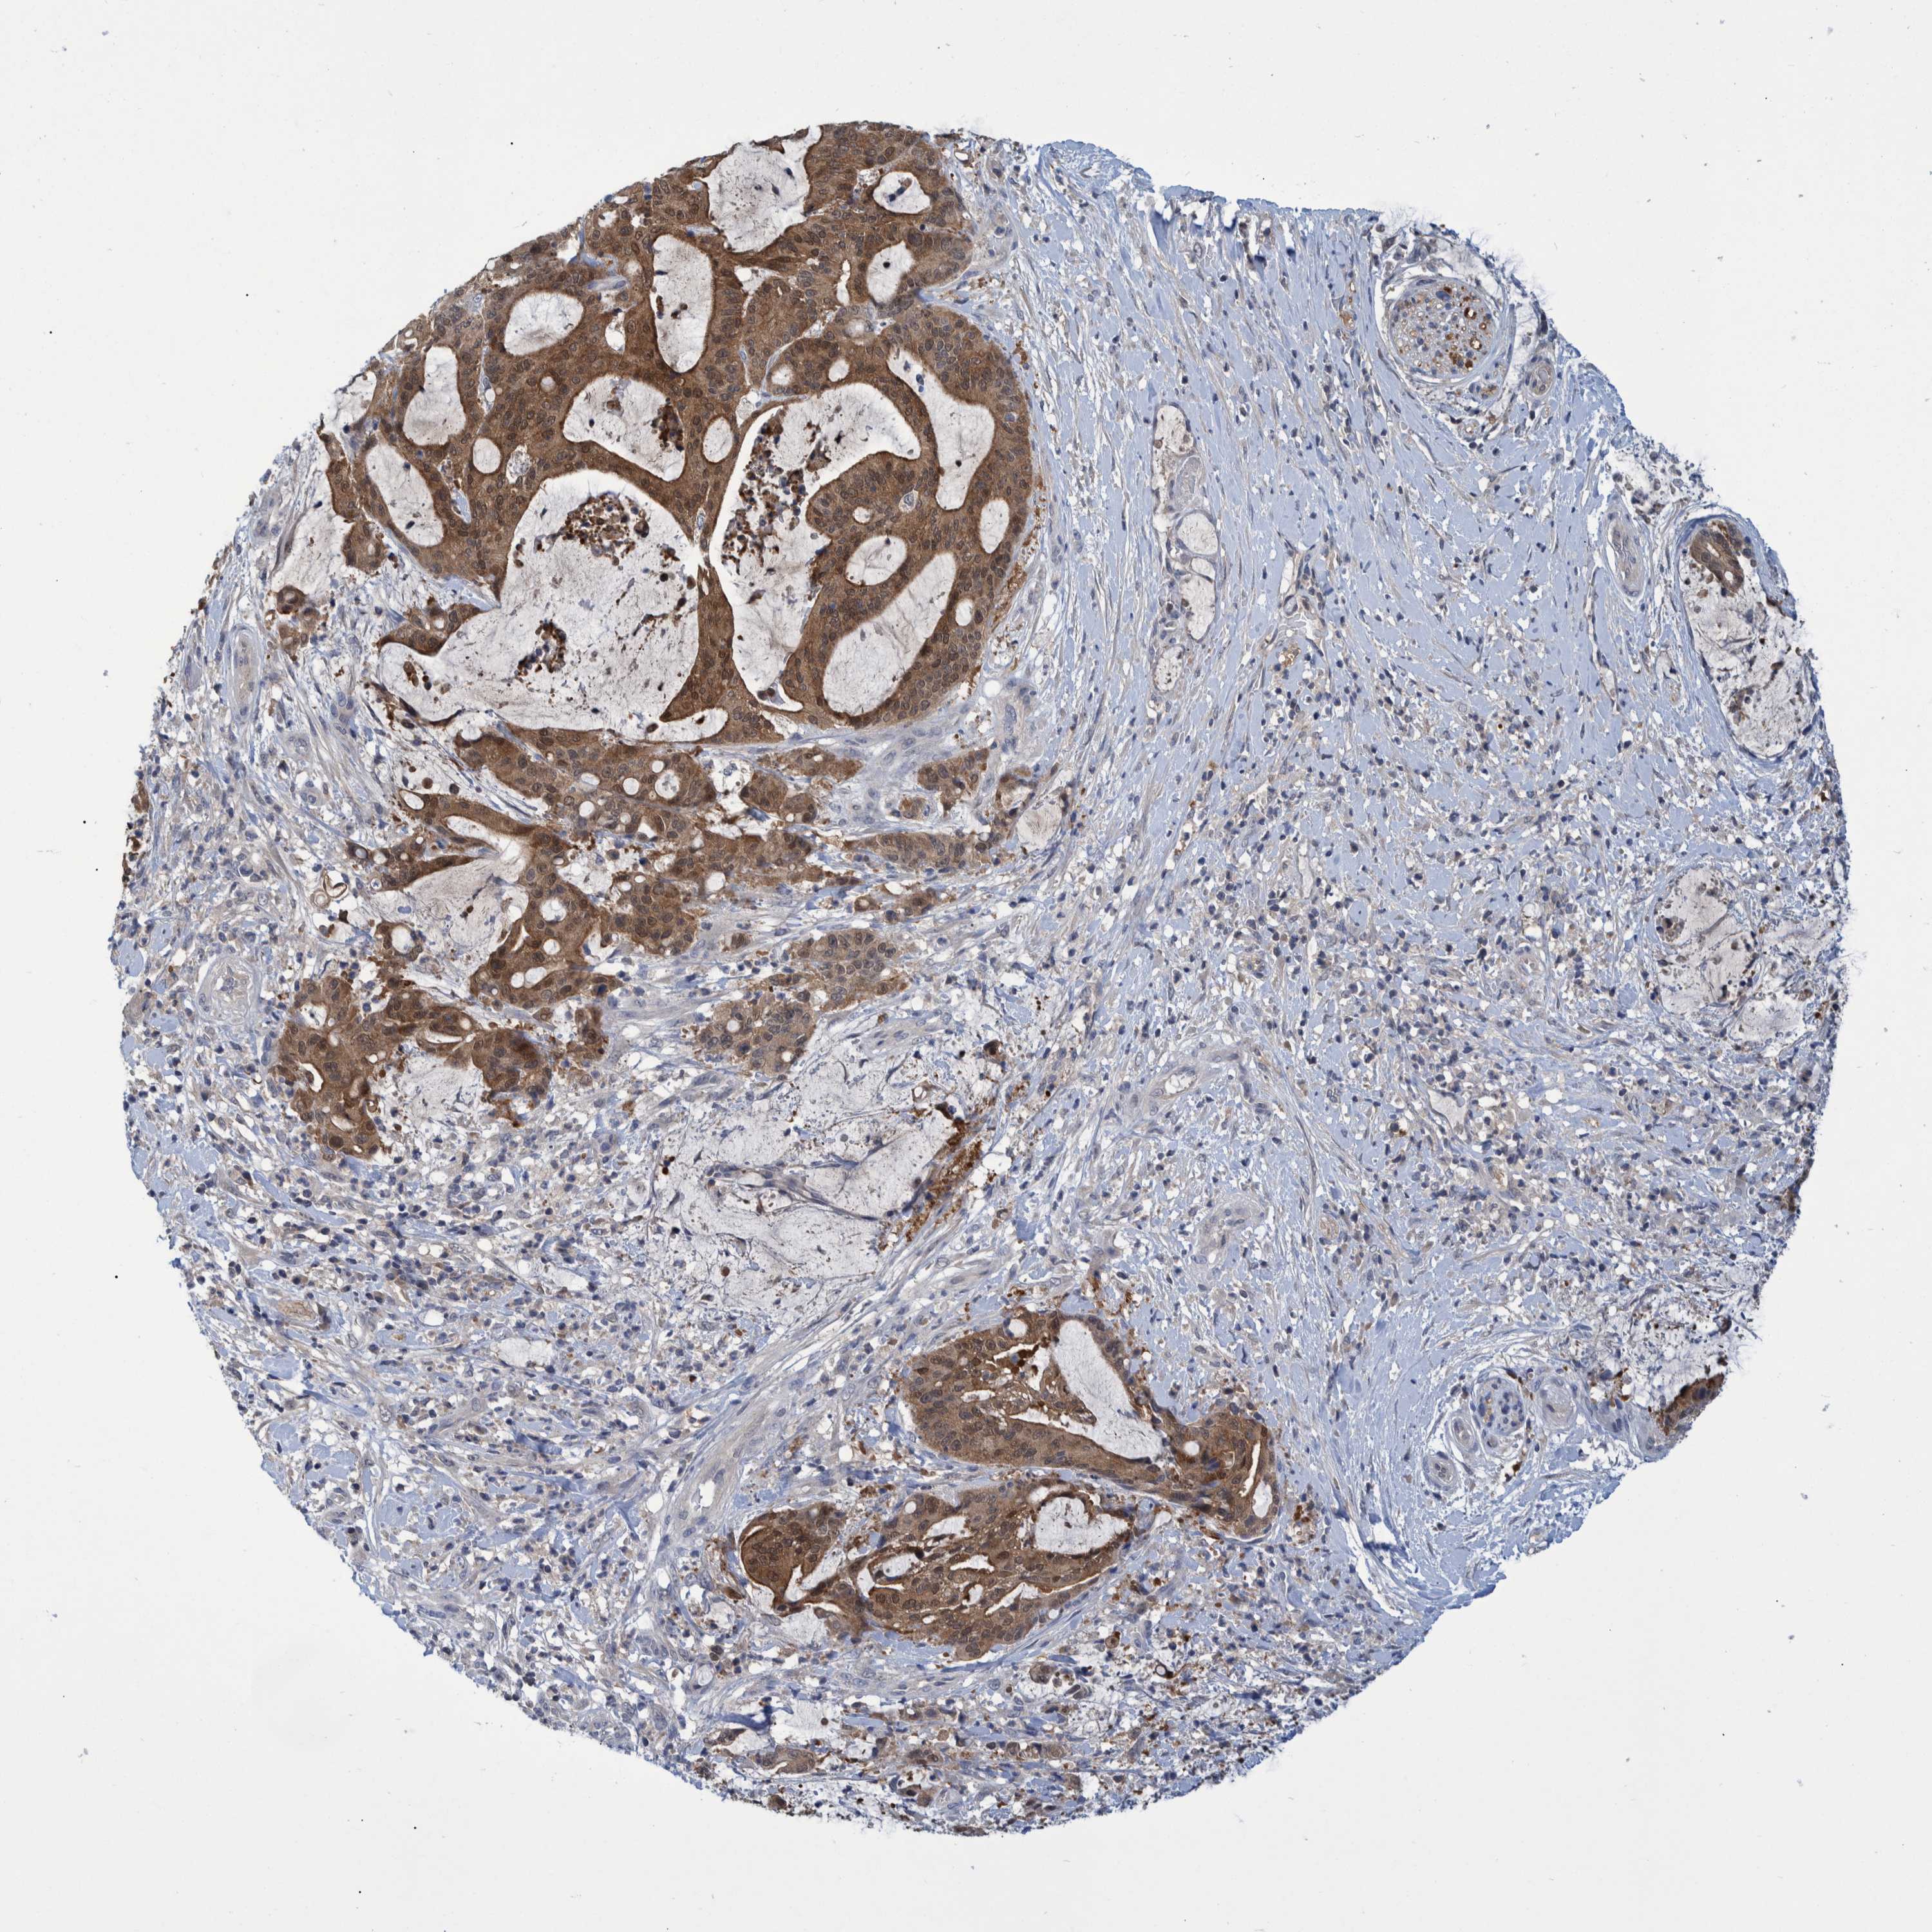

LIVER CANCER - Protein expressioni

A mouse-over function shows sample information and annotation data. Click on an image to view it in a full screen mode. Samples can be filtered based on level of antibody staining by selecting one or several of the following categories: high, medium, low and not detected. The assay and annotation is described here.

Note that samples used for immunohistochemistry by the Human Protein Atlas do not correspond to samples in the TCGA dataset.

Antibody stainingi

Antibody staining in the annotated cell types in the current human tissue is reported as not detected, low, medium, or high, based on conventional immunohistochemistry profiling in selected tissues. This score is based on the combination of the staining intensity and fraction of stained cells.

Each image is clickable and will lead to virtual microscopy that enables deeper exploration of all samples and also displays staining intensity scores, fraction scores and subcellular localization as well as patient and tissue information for each sample.

Antibody HPA023033

Antibody HPA023034

Staining

High

Medium

Low

Not detected

Intensity

Strong

Moderate

Weak

Negative

Quantity

>75%

75%-25%

<25%

None

Location

Nuclear

Cytoplasmic/membranous

Cytoplasmic/membranous,nuclear

Cholangiocarcinoma

Carcinoma, Hepatocellular, NOS